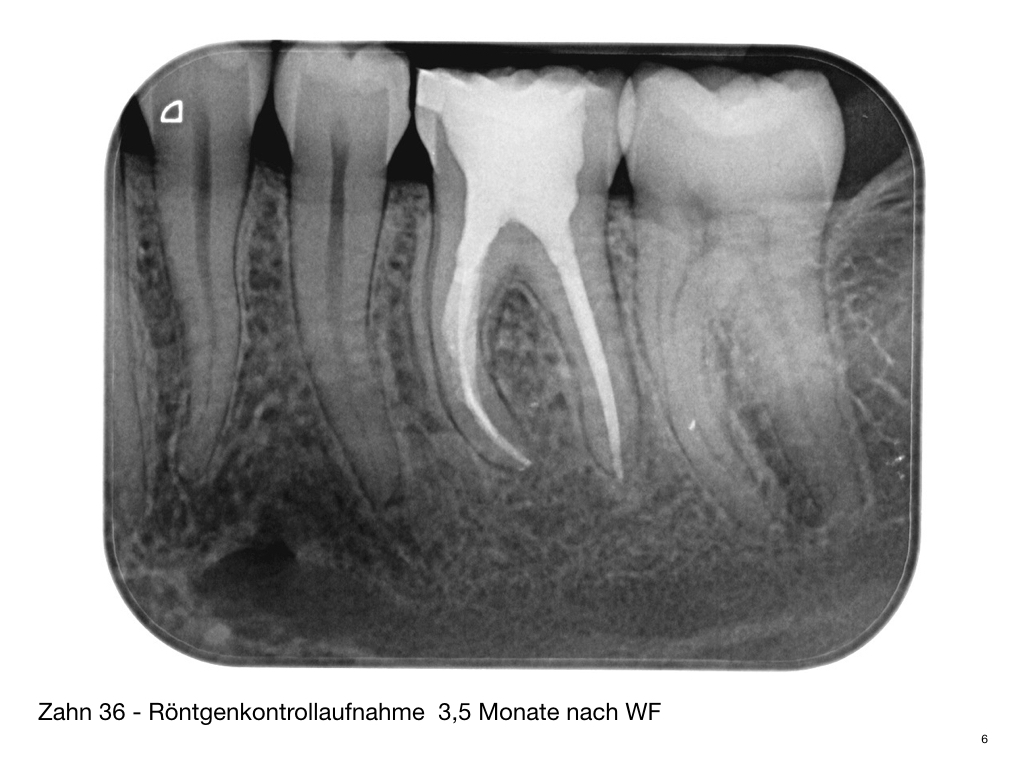

Calciumhydroxid – Überpressung (1)